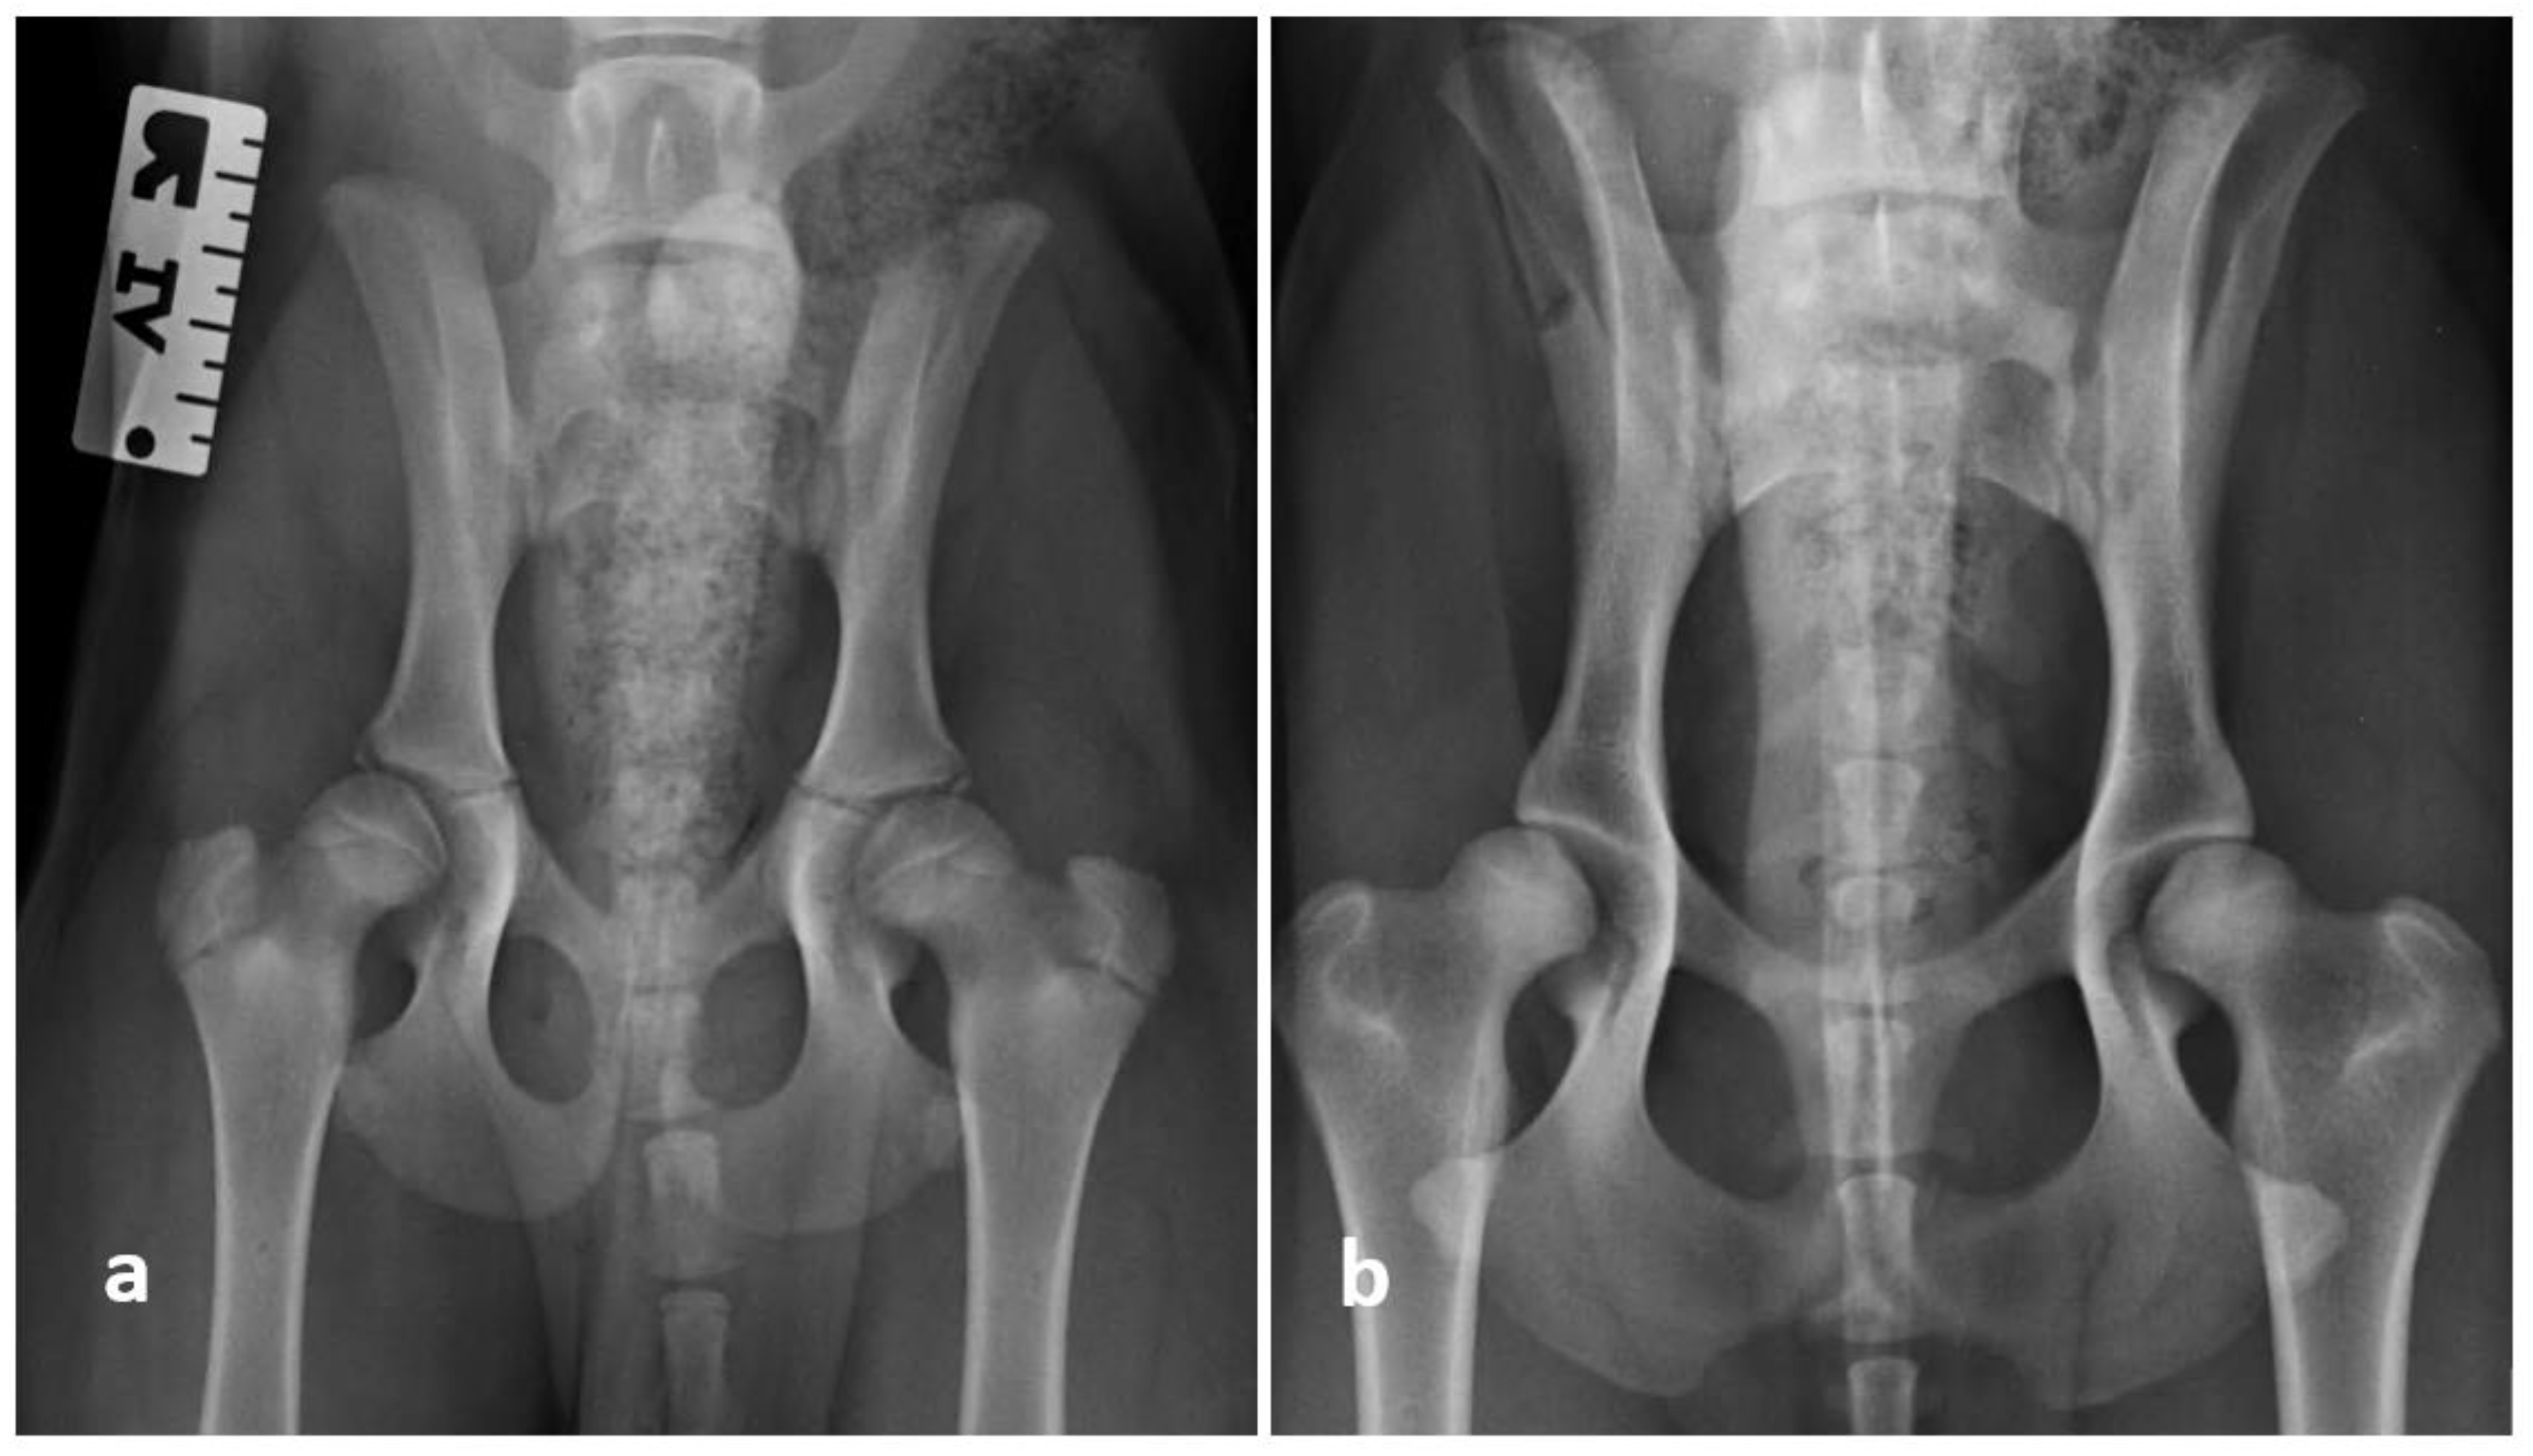

The dogs were graded from HD A to HD E according to FCI. Dogs with no hip dysplasia were categorized as category A, while dogs with nearly normal hip joints were rated as HD B. Dogs with mild, moderate, and severe grades of hip dysplasia were categorized as HD C, D, and E, respectively. All examinations were performed by the same investigator, who has been a certified scrutinizer for over 12 years (M.G.). The magnification of an extended ventrodorsal view of the right and left hip joints of two Rottweilers is shown in Figure 1. The final FCI grading was done at the age of 52 weeks (one year).

Figure 1.

Magnification of an extended ventrodorsal view of the right and left hip joints of two Rottweilers: (a) A dog at the age of 31 weeks, and (b) the same dog at the age of 52 weeks. The joint was consistently graded as HD A for this dog. (c) Another dog at the age of 18 weeks, and (d) the same dog at the age of 30 weeks. The joint was consistently graded as HD E and unsurprisingly, did not improve with continuous age.